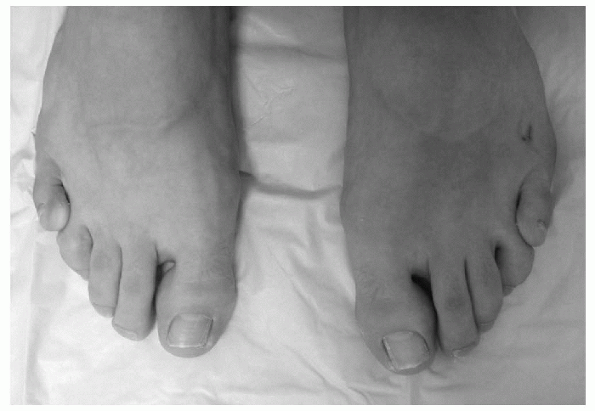

![]() |

Figure 4.2-1 (A) Six-week-old boy with bilateral clubfoot. Note the cavus, adduction, varus, and equinus position of the foot. (B) The arrow indicates a medial crease in the midfoot.